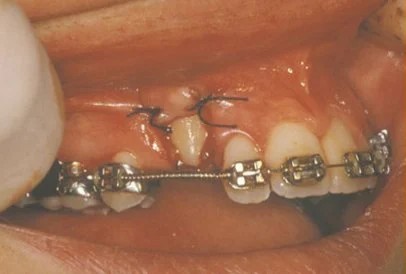

Exposure and bracketing of an impacted cuspid

Impacted canine surgery

The surgery to expose impacted canines takes just about 45 minutes. It is a comfortable procedure that is done under local anesthesia. Mild swelling and soreness may occur for several days following, and can be managed adequately with over the counter pain medicines. During the surgery, the crown of the tooth is uncovered. Depending on the severity of impaction, we may attach a bracket and gold chain to the tooth to “pull” it into place, or we may simply apply a dressing and let it find its own way. It is important to maintain good dental hygiene as part of your home care practice. We will schedule a follow up appointment about a week after surgery to check on your healing.